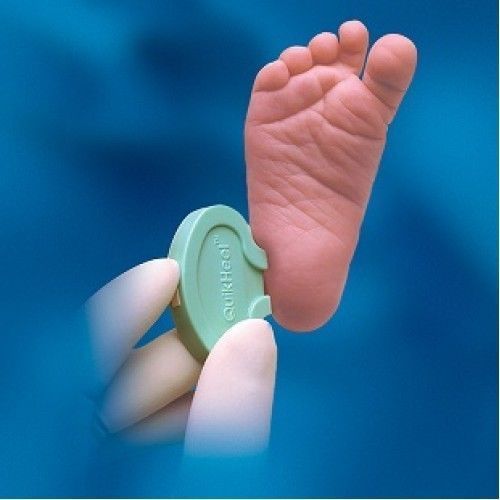

BD Microtainer Quikheel Preemie Lancet - 0.85mm x 1.75mm, Lavender, Pack Of 10